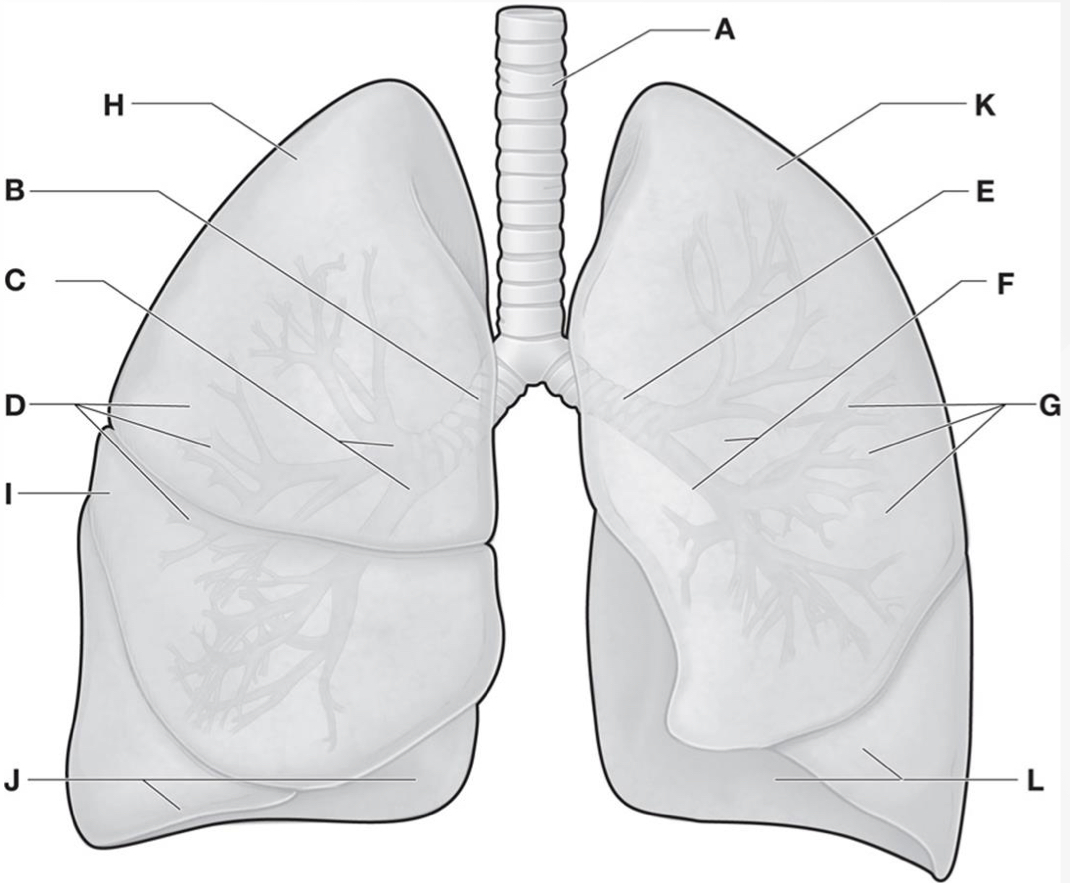

Which letters are the Horizontal & oblique fissures of the Right lung?

A & D

Which letters are the Superior, middle, & inferior lobes of the Right lung?ย

B, C, & E

Which letter is the Oblique fissure of the Left lung?

G

Which letters are the Superior & inferior lobes of the Left lung?ย

F & H

Which letters are the R. & L. Upper lobes of the Lungs?

H & K

Which letters are the R. & L. Lower lobes of the Lungs?

J & L

Which letter is the Middle lobe of the Right lung?

I